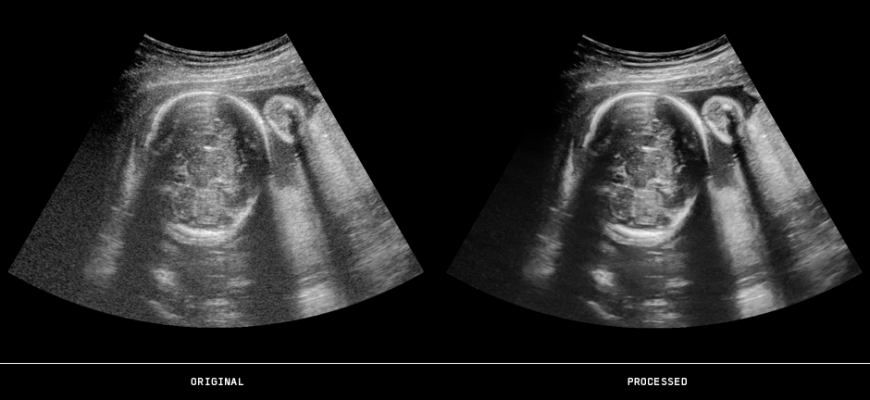

US PLUSView allows OEMs to provide a full range of ultrasound image enhancement capabilities, including deeper penetration, edge sharpening, contrast enhancement and improved speckle reduction features for technically difficult patients.

GOPiCE US (3-D/4D) is the industry’s first ultrasound real-time three-dimensional filtering product. Clinical evidence from recent years confirms that volumetric acquisitions with multi-dimensional image enhancement lead to faster and more accurate diagnoses. GOPiCE US in 3-D fetal ultrasound examinations has also clearly demonstrated a superior visualization of subtle fetal brain defects and other anomalies.